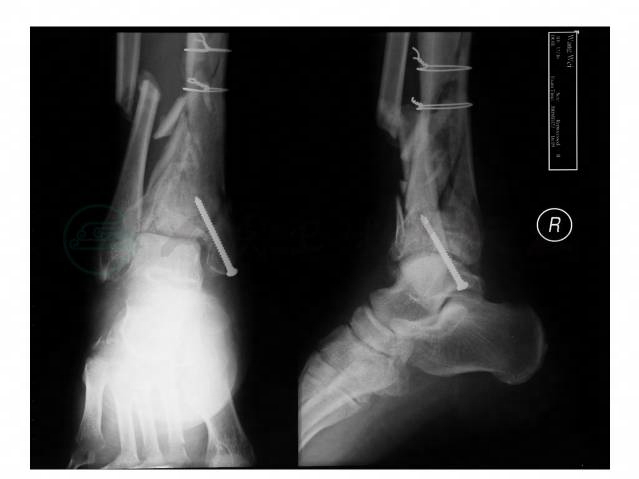

右踝关节X线片(图3):胫骨远段粉碎骨折,骨折累及长度9cm,骨折近端以2个钢丝环固定,内踝以一枚螺丝钉固定,骨折线清晰,胫骨略呈外翻。腓骨于踝关节水平8cm以近骨折,骨折远端呈向内短缩移位。

图3 右踝X线片